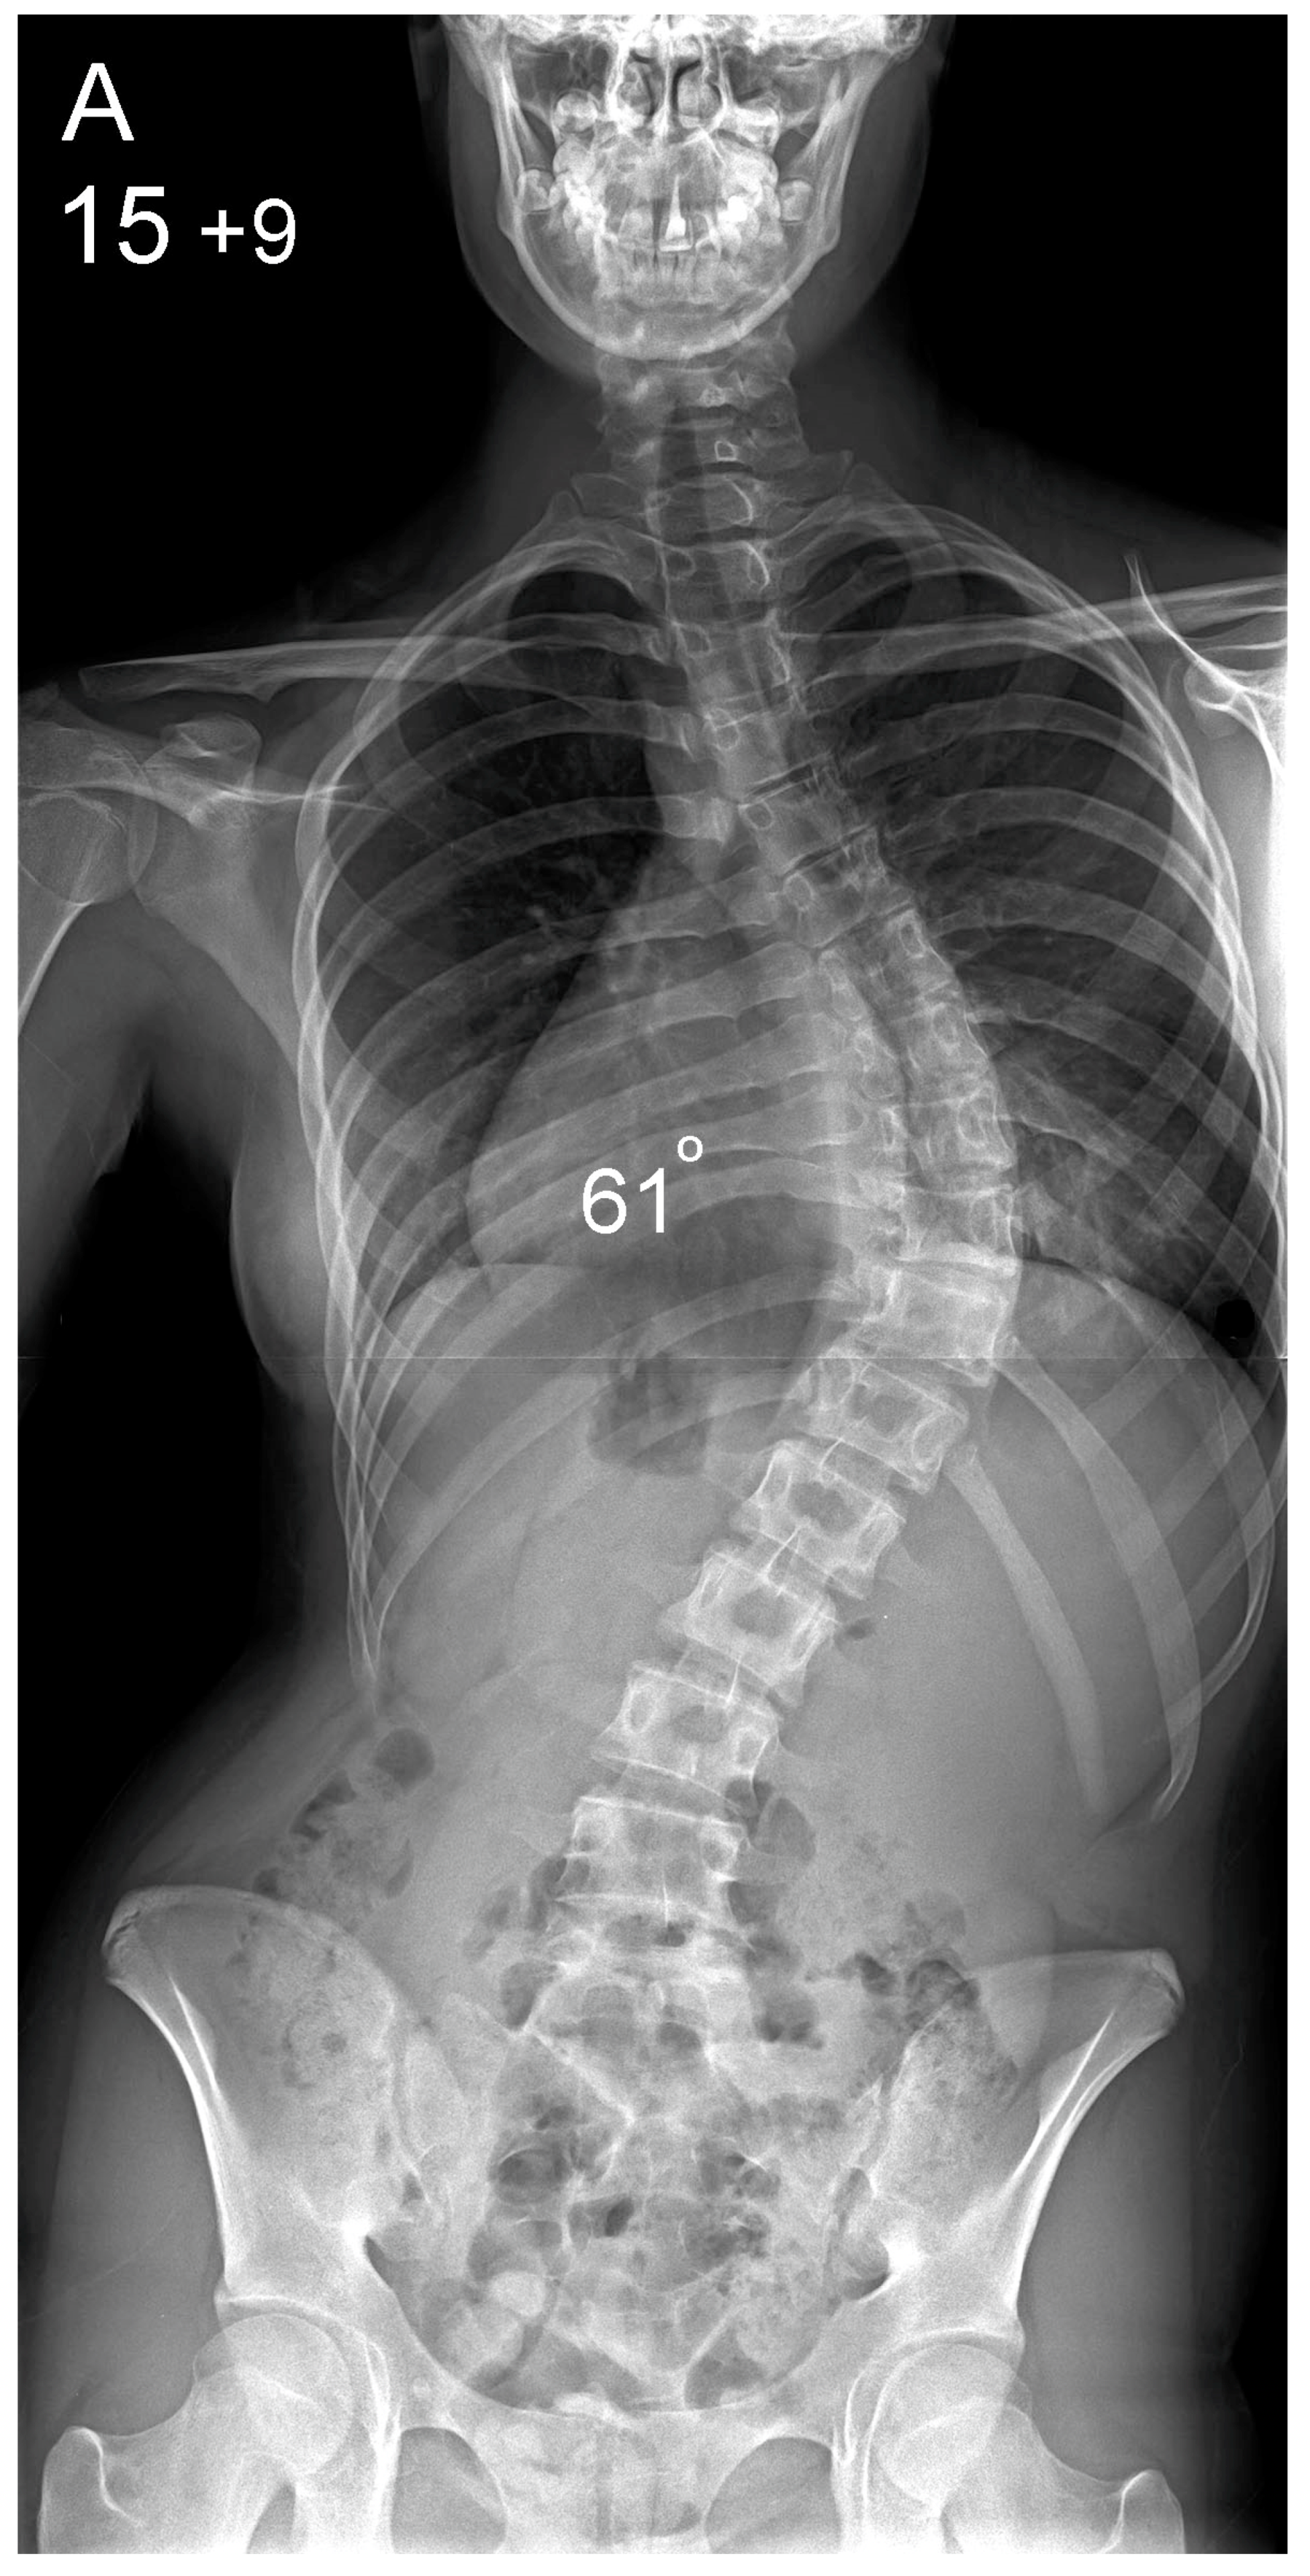

| Main thoracic scoliosis mean (range) | 64° (44–90) | 62° (42–94) | 0.31 | |

| Preoperative (°) | 64 (44–90) | 62 (42–94) | 0.31 |

| Postoperative (°) | 14 (0–44) | 16 (2–40) | 0.1 |

| Correction Index (%) | 78 (42–100) | 75 (50–96) | 0.07 |